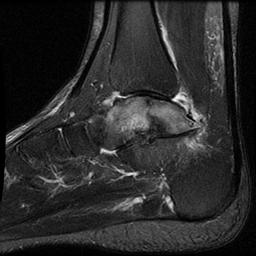

CT

Complications

Non / malunion of nonoperatively treated talar fracture

Malunion / AVN